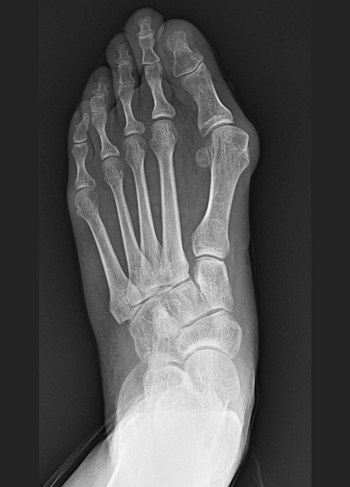

무지외반증은 엄지발가락이 두번째 발가락 쪽으로 심하게 휘어져 엄지발가락 관절이 돌출된 상태를 의미합니다. 심한 경우 엄지발가락과 두번째 발가락이 교차할 정도로까지 변형이 나타나기도 합니다. 30대 이상의 여성에게서 주로 발생합니다.

• 엄지발가락이 두번째 발가락 쪽으로 휘어지며 엄지발가락 관절 돌출

(1) 무지외반증 수술 전 (2) 수술 후 (3) 핀제거 후